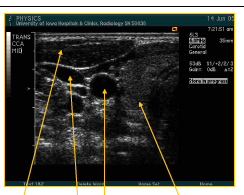

what are teh arrows pointing to here? what image is being taken?

trans CCA mid